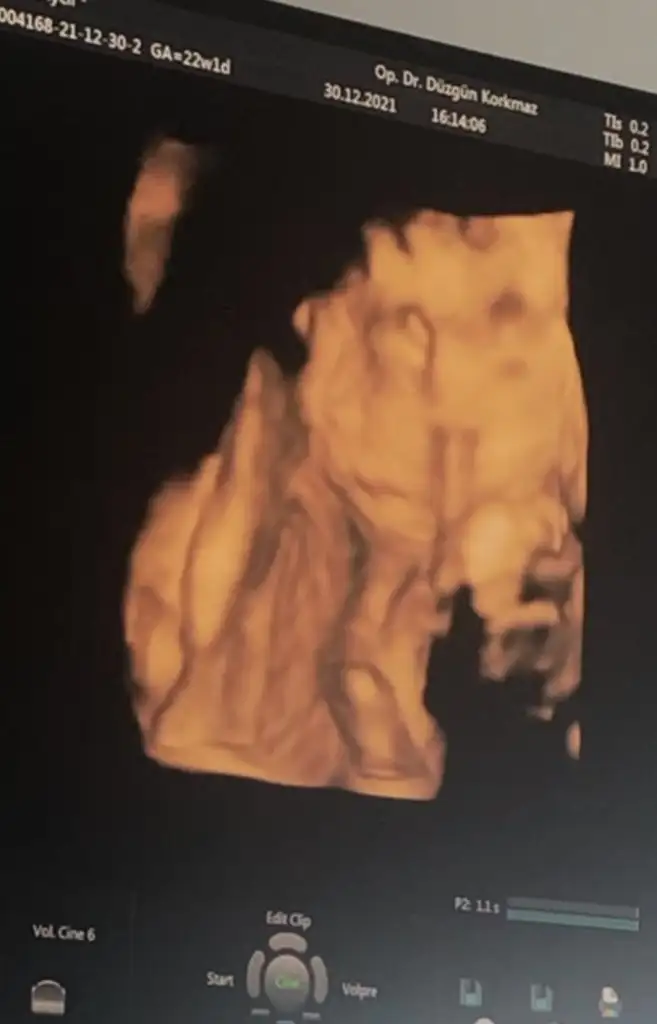

güzel şeyler bekliyor emin olGünaydıınnUyana uyana bir hal oldum Ben randevumu oluşturduğumda 16+3tüm 21+1ken gidicektim karantinadan dolayı 1 hafta ileri aldık bugün 22+1 olduk bakalım bizi neler bekliyor

Bu haftalarda görülen parlaklıklar genelde ilerleyen haftalarda kayboluyormuş canım inşallah 4 hafta sonra tertemiz görmek kısmet olurKızlar selam. Dün ilk doz tetanoz aşımı oldum. İki hafta sonra covid 3. dozu ondan iki hafta sonrada tetanoz 2. dozu olucam. Detaylıya girdim herşey yolunda ama bi tek kalbinde parlaklık gördü. 4 hafta sonra tekrar kontrol edelim dedi. Allah'ım bir hareketler elleri ayakları kıpır kıpır sürekli dönüp durdu detaylıda çok uzun sürdü o yüzden. Zaten hareketleri dışarıdan net bi şekilde görülüyo son 2 haftadır. Rabbim hepimizin meleklerini korusun. Şuraya fındık burunlu oğluşumun resmini de bırakayımEki Görüntüle 2978767

Çok şükür her şey yolunda kızlarkaç gündür kuduran oğluşun bugün yüzüstü yatıp kendini kapatacağı tuttu 504 gram olmuşuz bende 3 kilo almışım inanamıyorum. 2 hafta sonra kendi doktoruma randevumuz var